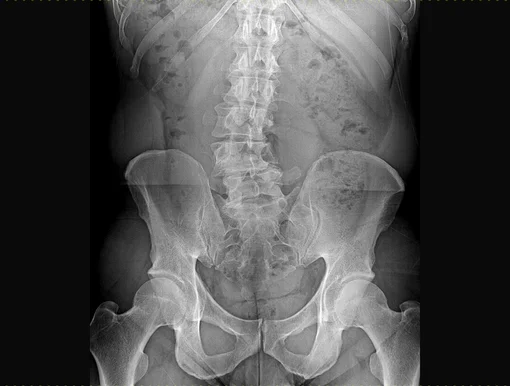

Sliding of the vertebral body (spondylolisthesis) can be divided into different groups. The most common causes are congenital or acquired conditions and generally occur in younger patients. However, with increasing age, the degenerative form of spondylolisthesis also plays a role. The main result is always instability with relating symptoms and the development of spinal stenosis. Decisive for this type of instability is that it is always characterized by a forward sliding of the upper vertebra against the lower vertebra.

Development of a complex deformity of the spine in the form of scoliosis is subject to various causes. Scoliosis is characterized by a complicated incorrect rotation of individual vertebrae in the longitudinal axis, with subsequent lateral curvature of the affected spinal region. Significant deformities of the lumbar spine occur, which again result in lateral and/ or central narrowing of the spinal canal (lateral or central stenosis).